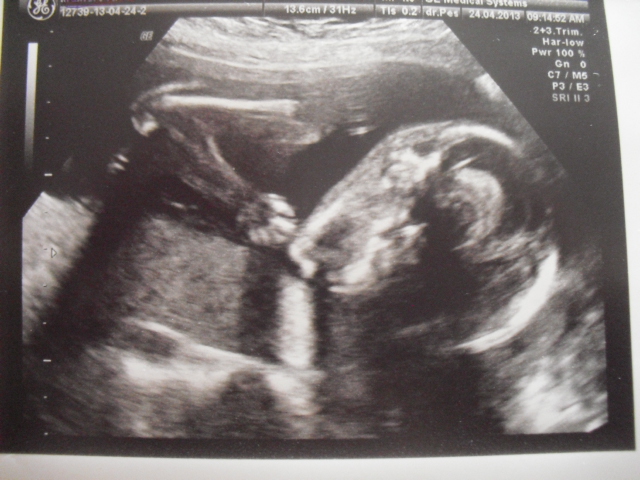

Tady Vám přikládám nějaké fotečky z UTZ, sice nejsou úplně nová, ale alespoň nějaké! Ať vidíte, jak nám maličký roste!

Jinak krany fotečky,je vidět jak hezky roste